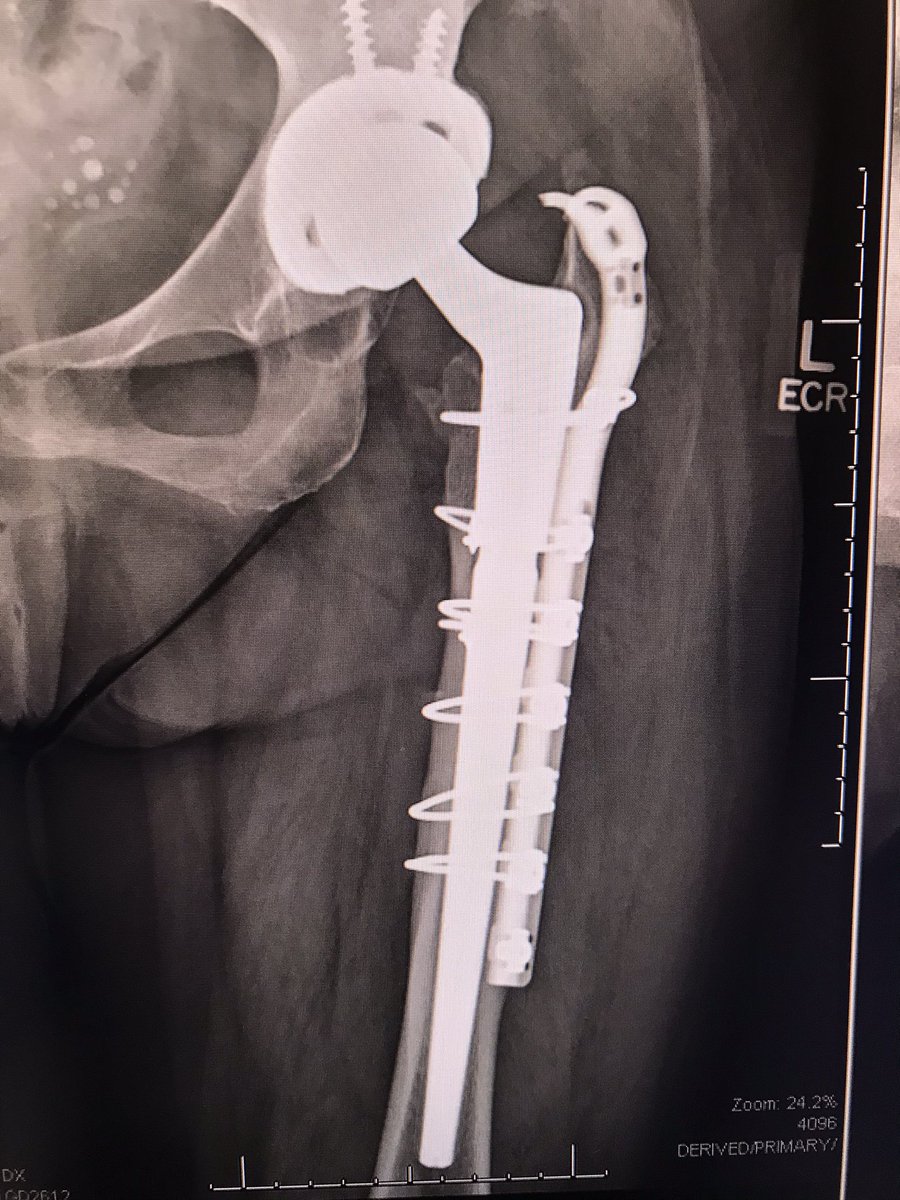

When a patient presents to the clinic w/this X-ray. That cup should be easy to remove. Anyone else ever see that stem fracture like that? Had to ETO to get it out.

Distal fragments identified with David A. Molho, M.D. . Fx all the way to distal lateral metaphysis with comminution there. Canal re-established over a long reamer and wired anatomically.

Distal fragments identified with <a href="/TotalHipKnee/">David A. Molho, M.D.</a> . Fx all the way to distal lateral metaphysis with comminution there. Canal re-established over a long reamer and wired anatomically.